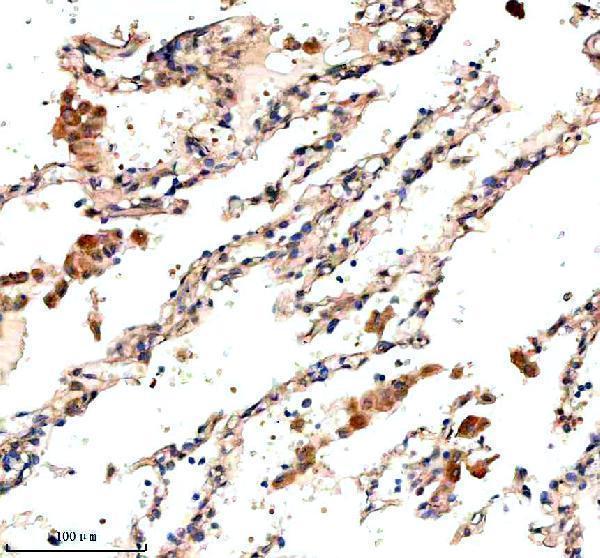

IHC analysis of NRAS using anti-NRAS antibody (A00099-3).

NRAS was detected in a paraffin-embedded section of human lung cancer tissue. Heat mediated antigen retrieval was performed in EDTA buffer (pH 8.0, epitope retrieval solution). The tissue section was blocked with 10% goat serum. The tissue section was then incubated with 2 μg/ml rabbit anti-NRAS Antibody (A00099-3) overnight at 4°C. Peroxidase Conjugated Goat Anti-rabbit IgG was used as secondary antibody and incubated for 30 minutes at 37°C. The tissue section was developed using HRP Conjugated Rabbit IgG Super Vision Assay Kit (Catalog # SV0002) with DAB as the chromogen.